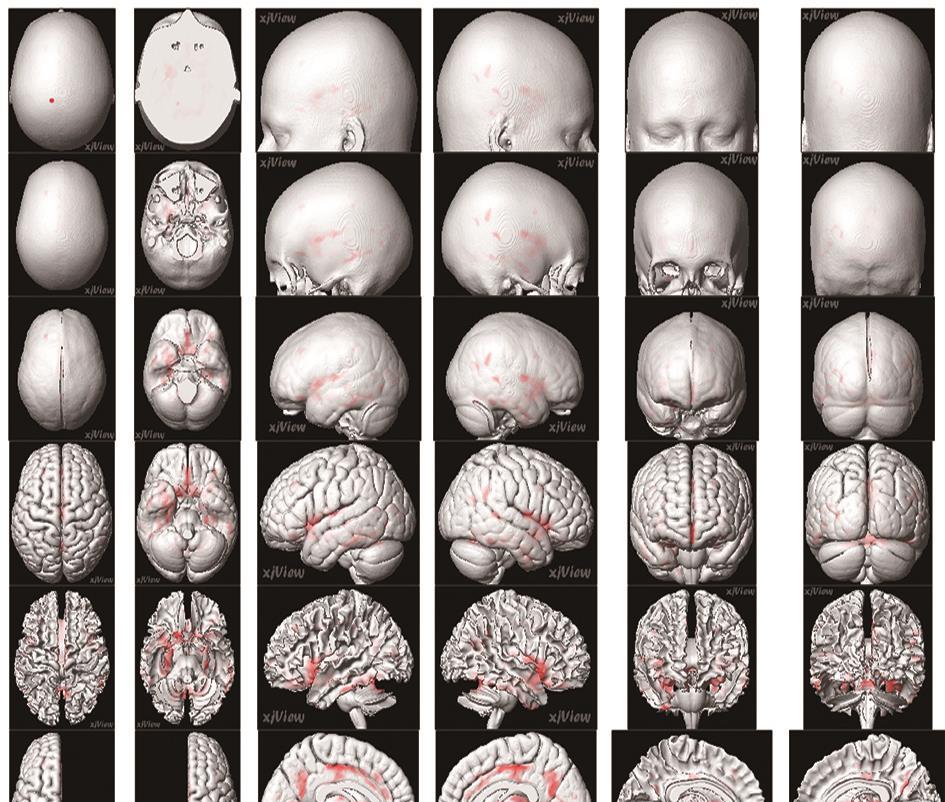

• 正常成人与伴吞咽障碍的急性脑梗死患者吞咽相关脑功能区激活机制的血氧水平依赖功能磁共振研究

2022, 47(7):802-810. DOI: DOI:10.13406/j.cnki.cyxb.003057

摘要:目的 运用血氧水平依赖功能磁共振(blood oxygenation level dependent-functional magnetic resonance imaging,BOLD-fMRI)技术对伴吞咽功能障碍的急性脑梗死患者和正常成人在吞咽活动时相应的脑功能区域激活特点进行研究,探索急性脑梗死患者吞咽功能障碍恢复过程中相关的脑功能区域调控方式。方法 选取2018年7月至2021年7月在昆明医科大学附属延安医院住院的伴吞咽障碍的急性脑梗死患者150例和正常成人100例,对其进行BOLD-fMRI扫描,记录两者在吞咽活动时相关脑功能区域的激活体积和强度,并对比两者间的差异。结果 共收集病例组150例,其中右侧脑梗死组患者50例,男29例,女21例,平均年龄(56.22±7.33)岁;左侧脑梗死组患者100例,男61例,女39例,平均年龄(58.07±6.84)岁;对照组100例,男57例,女43例,平均年龄(53.56±11.41)岁。对照组吞咽活动时激活的相关脑功能区域特点显示:两侧初级运动皮层中枢(BA4区)、运动前区/辅助运动区(BA6/8区)、缘上回(BA40区)、岛叶(BA13区)、颞上回(BA22区)、扣带回皮层(BA24区)、额叶内侧面(BA32区)、延髓、脑桥、基底核团、丘脑、小脑及左侧颞极(BA38区)和右侧颞横回(BA41区)等脑功能区激活体积和强度增加,左侧BA4区、BA40区、小脑激活体积较右侧大,差异有统计学意义(P<0.05);左右两侧脑区的激活强度差异无统计学意义(P>0.05)。右侧脑梗死病例组患者BOLD-fMRI扫描各脑区激活体积显示:右侧BA4区、BA6/8区激活体积较对照组减小,左侧BA6/8区、BA4区激活体积较对照组增大,双侧后扣带回皮层的BA23和顶叶内侧面BA31区体积较对照组增大,左侧视觉中枢的BA18/19和BA41区皮层激活体积较对照组增大,差异有统计学意义。右侧BA4区、BA6/8区、BA40区、BA13区激活强度较对照组降低,差异有统计学意义。左侧脑梗死病例组患者BOLD-fMRI扫描各脑区激活体积显示:左侧BA4区、BA6/8区的激活体积较对照组减小,右侧BA4区、BA6/8区激活体积较对照组增大,双侧BA23/31区、左侧BA41区、双侧BA7区、双侧BA18/19区和双侧小脑激活体积较对照组增大,差异有统计学意义。左侧BA4区、BA6/8区、BA40区、BA13区激活强度较对照组降低,差异有统计学意义。结论 双侧运动、运动前、感觉、嗅觉、听觉、脑干、小脑、基底核团等脑功能区均参与调控正常人的吞咽活动,且调控具有一定的偏侧性。同侧的运动功能区、运动功能前区激活体积降低,对侧运动功能区、运动功能前区激活体积增加是伴吞咽障碍的急性脑梗死患者吞咽相关脑功能区的主要代偿特点。